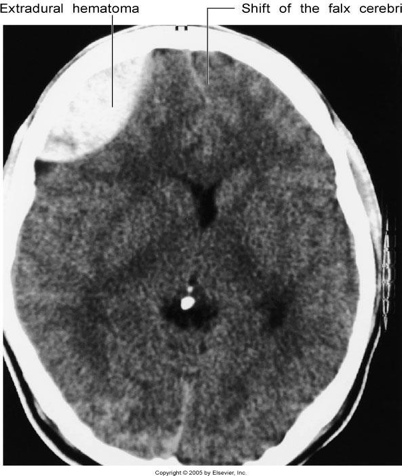

What type of haemorrhage can be seen in this CT scan?

Extra-dural haemarrhage caused by injury to the MMA